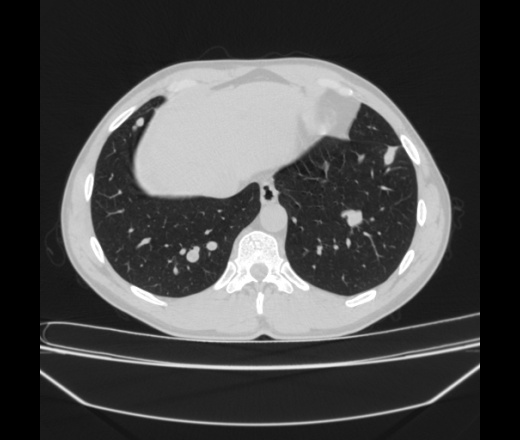

Молодой мужчина. Монтер путей. Жалоб нет. Ни чем не болел и ничего не беспокоит. Год назад при прохождении ФГ в легких были выявлены плотные очаговые и фокусные тени с четкими ровными контурами, рентенологом была выставлено заключение БОИ после твс. Больного обследовали, кровь моча б/о. Консультировали у фтизиатра, в заключении остаточные изменения после твс.(все проходит в ЦРБ)  Через год, т.е сейчас приходит на плановое ФГ где выявляют эти же тени но в большем количестве, и уже другой человек пишет мтс, рекомендует КТ. Больной снова сдает АОК, ОАМ которые абсолютны идеальны, других методов обследования не назначали. Жалоб никаких.

Помогите разобраться с данными образованиями, не встречал и не знаю о таких, что это кисты?, аневризмы? Расположены по ходу сегментарных и субсегментарных артерий, имеют плотность от -3 до +5 Ед.Н.

Первая мысль была о ретенционных кистах, но как бы связаны с сосудами. Может аневризмы? Контраст надо ввести

Я скажем так в замешательстве, плотность жидкости наталкивают думать об кистах, но связь с сосудами это исключает; в то же время думать об аневризмах не позволяет думать такая низкая плотность.... Может я не прав, хз.  Да и появились они буквально за год....

Эхинококкоз легких

ROI_888 прав, гидатитозный эхинококкоз вполне очень даже похож.

Не уверен, но есть впечатление о внутригрудной лимфоаденопатиии ( группа мелких лимфатических узлов).Не исключал бы вариант MTS, плохо что нет контраста. Попытался бы посмотреть нет ли увеличенных периферических лимфатических узлов, тогда можно бы было взять  из них  биопсию на гистологию.

Александр, я думал мтс обычно имеют мягкотканную плотность, да и структура у них как бы однородная. А здесь кругляки наполненые жидкостью, с утолщенными стенками, некоторые кругляки сливаются образуя несколько камер. Смущает тото факт что они по ходу сосудов. Может это связано с тем что распространение идет от легочного ствола, из правых отделов сердца, а туда они попадают если верить Тюрину из воротной вены (ну эт я в пользу гидатитозного эхинококка).

Неосложненный эхинококк может "жить" долго спокойно. Может расти потихоньку, бессимптомно. Так что , поддерживаю версию Роя